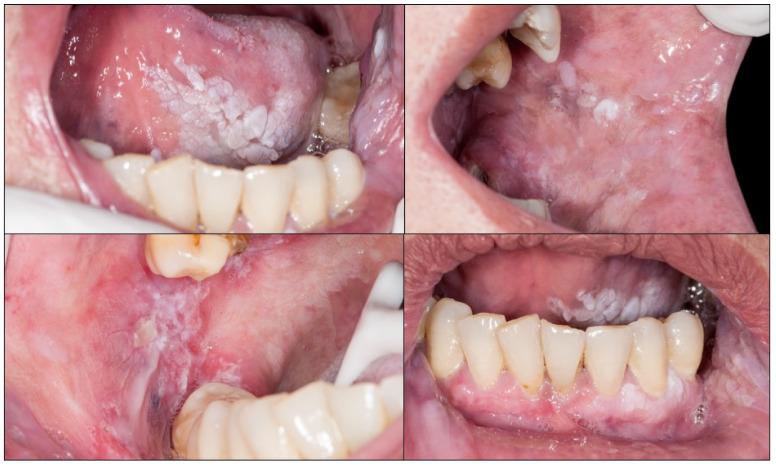

Oral cancer is a growing problem, accounting for 377,713 worldwide new cases per year, and 177,757 deaths annually and representing a 5-year mortality rate close to 50%, which is a considerable mortality that has not decreased substantially in the last 40 years. The main cause of this high mortality is related to the diagnosis of a high percentage of oral cancers in advanced stages (stages III and IV) in which treatment is complex, mutilating or disabling, and ineffective. The essential cause of a cancer diagnosis at a late stage is the delay in diagnosis, therefore, the achievement of the objective of improving the prognosis of oral cancer involves reducing the delay in its diagnosis. The reasons for the delay in the diagnosis of oral cancer are complex and involve several actors and circumstances-patients, health care providers, and health services. In this paper, we present the results of a scoping review of systematic reviews on the diagnostic delay in oral cancer with the aim to better understand, based on the evidence, and discuss in depth, the reasons for this fact, and to identify evidence gaps and formulate strategies for improvement.

口腔癌问题日益严重,全球每年有377,713例新发病例,177,757人死亡,5年死亡率接近50%,这是一个相当高的死亡率,在过去40年里并未大幅下降。这种高死亡率的主要原因与高比例的口腔癌在晚期(III期和IV期)被诊断有关,在这些阶段治疗复杂、致残或导致功能丧失且效果不佳。癌症晚期诊断的根本原因是诊断延迟,因此,实现改善口腔癌预后的目标涉及减少其诊断延迟。口腔癌诊断延迟的原因复杂,涉及多个因素和情况——患者、医疗服务提供者和卫生服务机构。在本文中,我们展示了一项关于口腔癌诊断延迟的系统评价的范围综述结果,旨在基于证据更好地理解并深入讨论这一现象的原因,识别证据空白并制定改进策略。